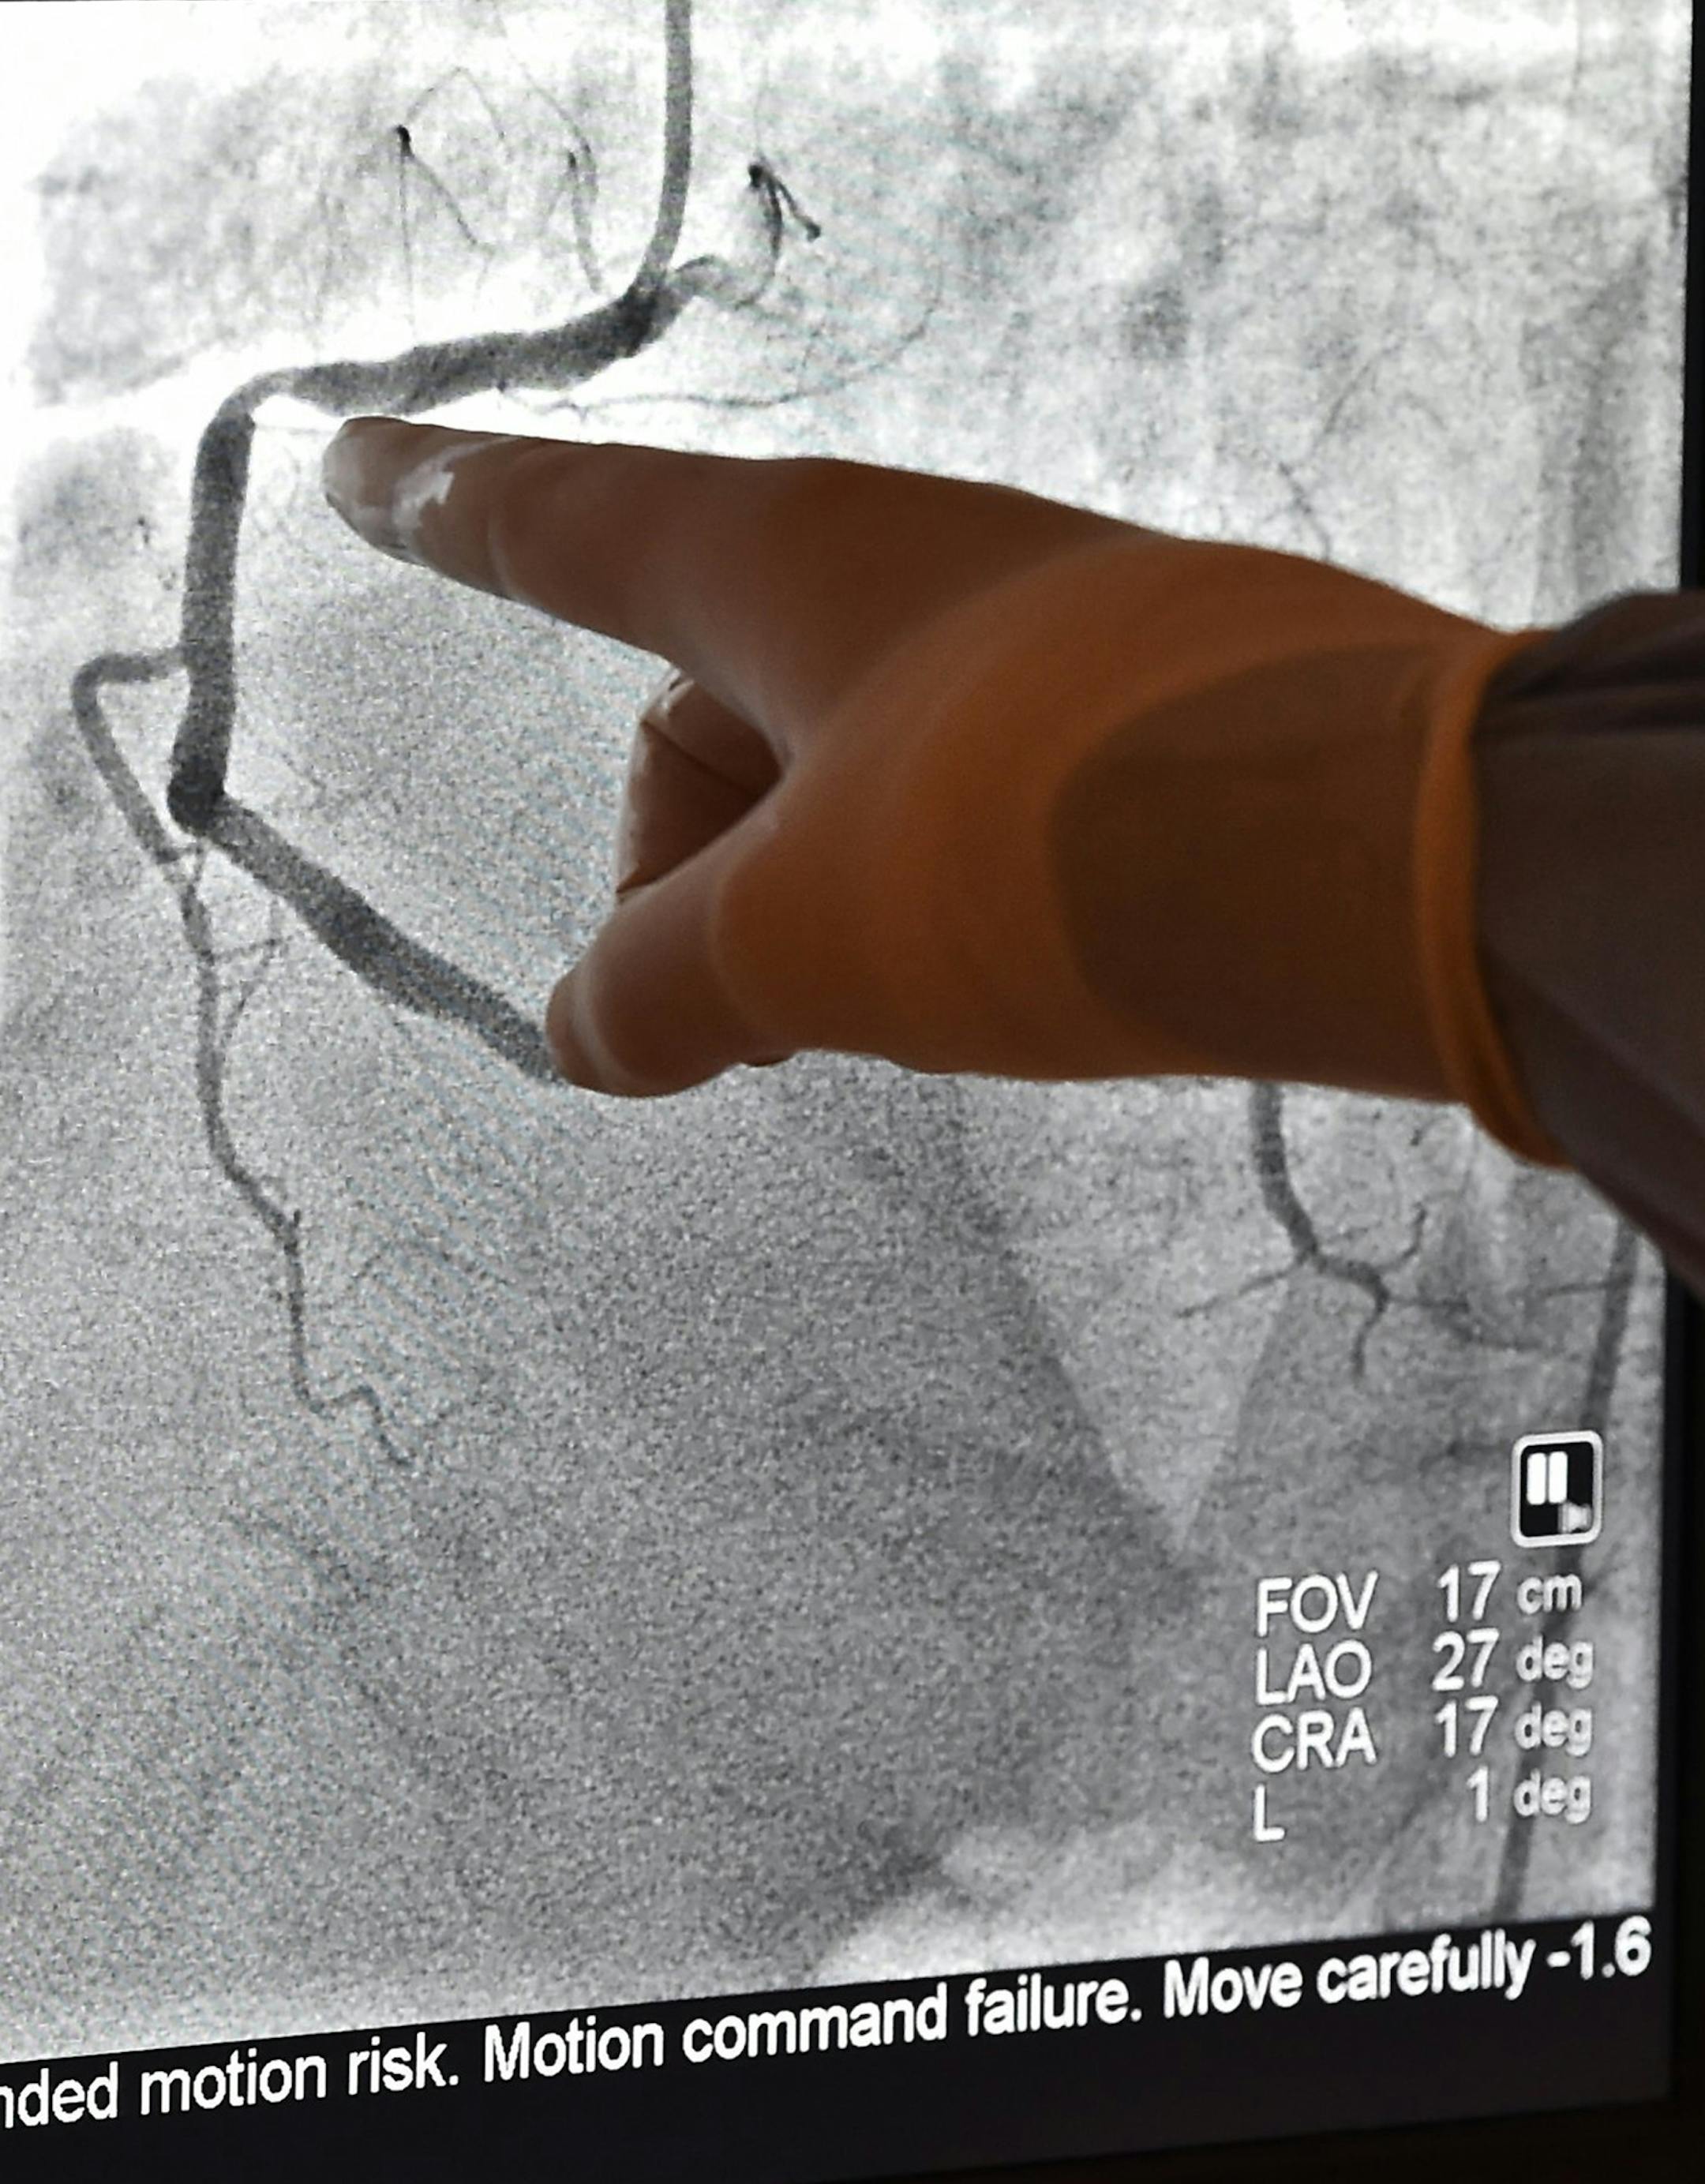

Kenneth Huber, an interventional cardiologist with Saint Luke's Mid America Heart Institute, points out the blockage in a patient's artery at Saint Luke's Mid America Heart Institute on November 25, 2015. Unnecessary angioplasties have declined in recent years. (Jill Toyoshiba/Kansas City Star/TNS) ORG XMIT: 1177325

A cardiologist pointed out the blockage in a patient’s artery at St.Luke’s Mid America Heart Institute in Kansas City, Mo. Elective angioplasties have declined in recent years. (The Minnesota Star Tribune)